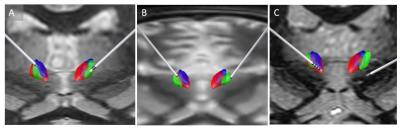

Figure 2A shows post-surgical CT reconstruction of a typical lead along with relevant thalamic nuclei (defined using the Morel atlas). The trajectory can be seen entering through ventral posterior lateral (VPL) level with contacts 2 and 3 inside the CM nucleus and the most inferior contact outside the CM, likely at the Pf interface. The Anteroventral (AV) and Pulvinar nuclei and the mammillothalamic tract (MTT) are also shown for reference. Figure 2B shows bilateral lead reconstructions for all patients shown relative to CM from the Morel atlas (magenta) and THOMAS atlas (cyan).

Figure 3 shows bilateral lead reconstruction for three individual cases (2 responders and 1 non-responder) with differing levels of agreement between the two atlases (red, violet) and patient-specific segmentation (green). In the first patient (A), there is good agreement with the three methods and this was also corroborated clinically based on patient response. In the second patient (B), the lead appears to be completely outside atlas-based CMs. The patient-specific segmentation (green) is, however, able to accurately capture the CM location and this was also corroborated clinically based on the response. In the third non-responder patient (C), the lead is outside both the atlas-based CMs and patient-specific CM. The mean distance between the center of mass of CM and active contact was 1 mm, 1.86 mm, and 1.31 mm for the patient-specific targeting, Morel atlas and Thomas atlas targeting respectively for the responders. For the non-responder, this was 8.1mm. 8.1mm and 7.1mm respectively

Figure 3. Three example cases with responders (A, B) and non-responder (C). A shows excellent agreement between patient-specific segmentation and atlases. B shows the lead outside the atlas-based CM but inside the patient-specific segmentation (green). C shows the electrode well outside CM for all 3 methods.